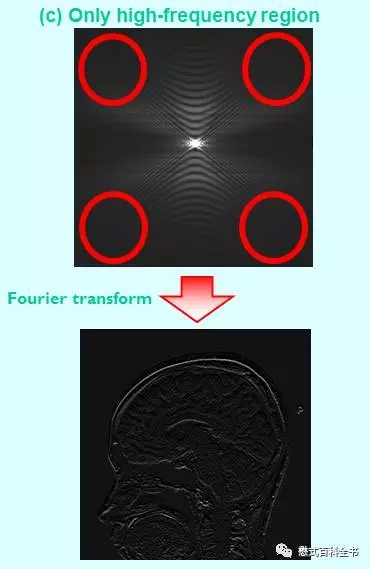

图15:只利用K空间周边数据,把中心部分数据丢弃,来重建图像。可以发现,重建图例的图像,周围有轮廓,有解剖细节,但是没有对比度,无论是脑脊液和脑实质,还是灰质白质,都没有对比度。